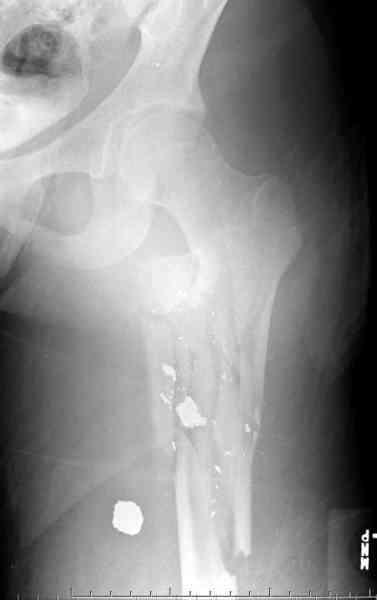

Молодой, с общим состоянием без проблем. Больной соперирован в день поступления и через два дня после операции выписан, так что не успел развиться гной.

Перелом низкоскоростным оружием, типа пистолетного, так что не стали гоняться за пулевыми фрагментами. С нервом пока подождем, иногда нерв восстанавливается если не прямое попадание в нерв, а "сотрясение" (shock wave injury).

Из всех типов фиксации взяли малоинвазивную технику мостовидной пластиной, использовали Locking проксимальную Synthes пластину.